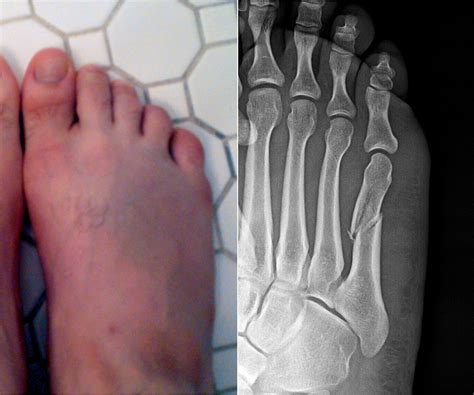

A hairline fracture, also known as a stress fracture, is a thin crack in the bone. In the case of a hairline fracture ankle, this crack typically occurs in one of the three bones that form the ankle joint: the tibia, fibula, or talus. These fractures are often caused by repetitive stress or a sudden impact, such as twisting the ankle or landing awkwardly after a jump.

Symptoms of a Hairline Fracture Ankle

Recognizing the symptoms of a hairline fracture ankle is the first step toward proper treatment. Common symptoms include:

• Pain that worsens with activity and improves with rest

• Swelling and tenderness around the ankle

• Difficulty bearing weight on the affected foot

• Bruising or discoloration

• Limited range of motion

Diagnosing a Hairline Fracture Ankle

Diagnosing a hairline fracture ankle involves a combination of physical examination and imaging tests. Your healthcare provider will likely perform the following steps:

• Physical Examination: The doctor will assess the affected area for swelling, tenderness, and range of motion.

• Imaging Tests: X-rays are the most common imaging test used to diagnose fractures. However, hairline fractures may not always be visible on initial X-rays. In such cases, additional imaging tests such as MRI or CT scans may be required.